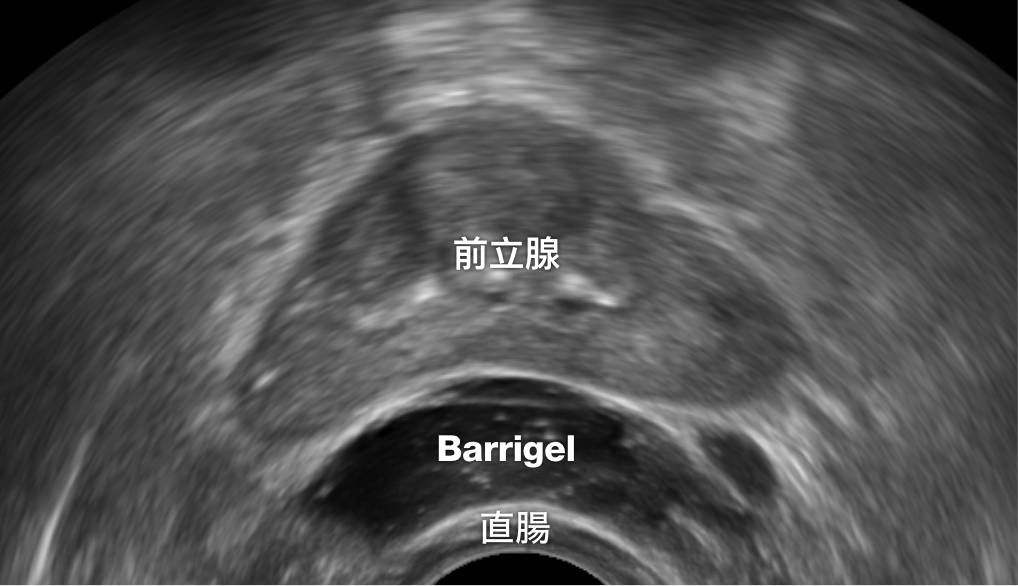

TRUS 画像

TRUS画像提供:Neil F. Mariados, MD

Radiation Oncologist; New York, United States